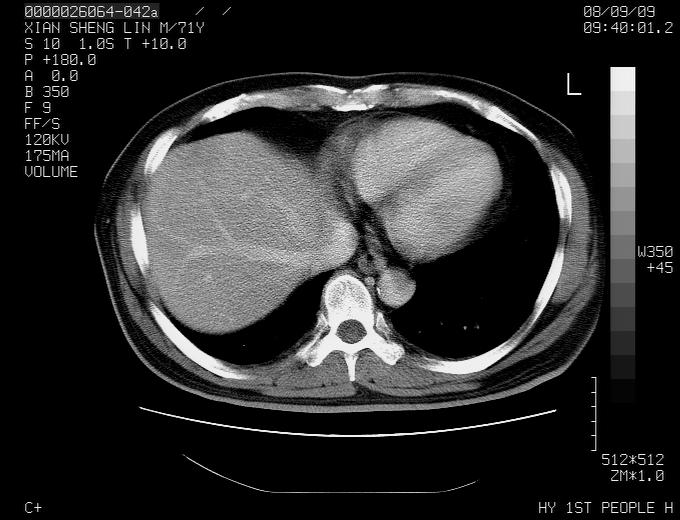

1,右肺中心型ca,气管隆突旁淋巴结转移。

2,右膈明显抬高,建议肝脏扫描排除转移或原发灶。